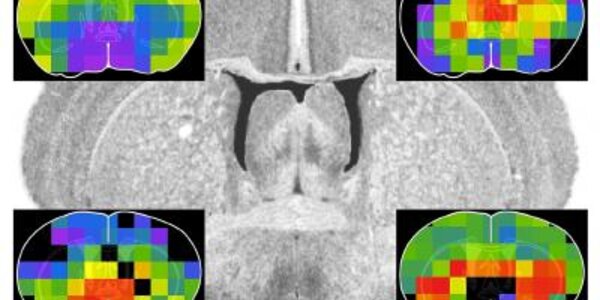

Google Your Brain

The Allen Brain Atlas, a genome-wide map of the mouse brain on the Internet, has been hailed as “Google of the brain.” The atlas now has a companion or the brain’s working molecules, a sort of pop-up book of the proteins, or proteome map, that those genes express. The protein map is “the first to apply quantitative proteomics to imaging,” said Richard D. Smith, Battelle Fellow at the Department of Energy’s Pacific Northwest National Laboratory, who led the mapping effort with Desmond Smith of UCLA’s David Geffen School of Medicine. Caption: Abundance profiles of four different proteins…